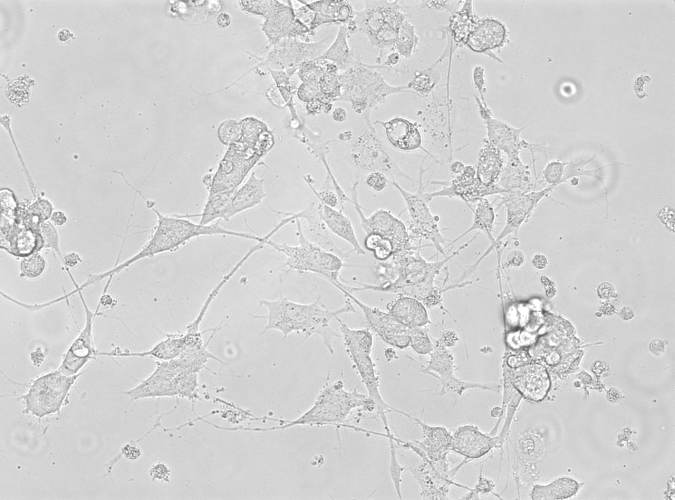

In vehicle-treated cells, MPP+produced significant morphology changes like cell shrinkage, loss in membrane structure and loss in cell number (fig. 1B). Treatment with Mimosa pudica restored the cell structure and increased the cell viability by alleviating MPP+ induced neurotoxicity in SHSY5Y cell lines.

Fig. 1(B): Various Treatment of Mimosa pudica and MPP+. MPP+ treated cells shows cell shrinkage and Mimosa treated cells shows protection on neurons